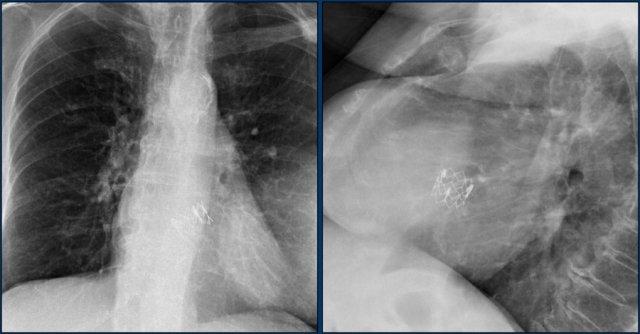

Hình ảnh bên trái cho thấy bệnh nhân có ICD được đặt đúng vị trí.

Vài tháng sau, thiết bị hoạt động không bình thường do hộp ICD và điện cực bị xoay (mũi tên vàng) và co rút lại (mũi tên trắng).